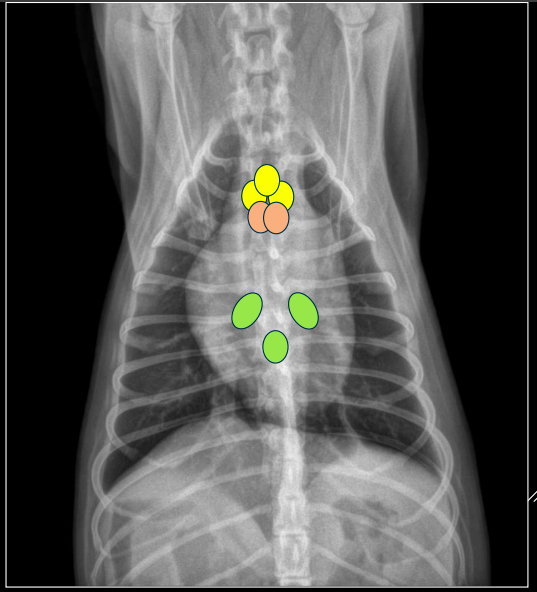

NÓDULOS LINFÁTICOS MEDIASTÍNICOS

- Mediastínicos craneales.

- Esternales.

- Traqueobronquiales.

Craneales: su aumento desplaza dorsalmente la tráquea (proyección LL).

Esternales: dorsal a la 2ª esternebra. Se ven muy bien

Traqueobronquiales: tres ganglios (derecho, izquierdo, medio) a nivel de la carina. Se ve algo peor

Timo

- LL: Solo se ve como una linea de tejido blando (hiperecoica) craneal al corazón

- VD: Ala de barco craneal y a la izquierda del corazón